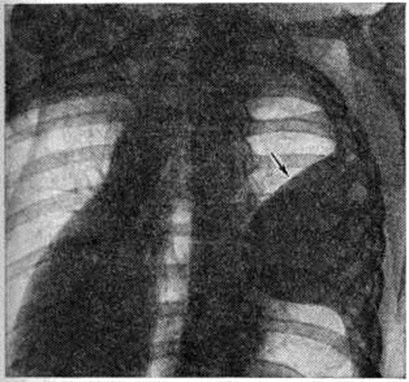

Выпотной Плеврит с накоплением серозного и серозно-фибринозного выпота является самым частым вариантом туберкулёзного Плеврит Наблюдается при образовании множественных туберкулёзных бугорков на плевре, иногда сливающихся между собой в более крупные очаги, а также при казеозном некрозе отдельных крупных очагов. Однако в этом случае в клеточном составе выпота преобладают нейтрофилы. При более распространённом казеозном некрозе плевры выпот становится серозно-гнойным, а при обширных поражениях — гнойным. В случае прорыва в плевральную полость субплеврально расположенных туберкулёзных очагов и каверн возникает обширный казеозный некроз плевры, сопровождающийся также экссудативной воспалительной реакцией плевры и накоплением выпота, нередко гнойного. При гнойном Плеврит (эмпиеме плевры) гнойный выпот скапливается преимущественно в нижних отделах плевральной полости. Гнойный Плеврит пневмококковой природы обычно сочетается с фибринозным выпотом и поэтому характеризуется скоплением гноя среди фибринозных «камер», располагающихся в нижних отделах плевральной полости. Стафилококки и стрептококки вызывают чисто гнойный Плеврит со скоплением жёлто-зелёного сливкообразного гноя в первом случае и жидкого серого — во втором. Плевра при этом тусклая, покрыта гноем, иногда некротизирована, пронизана колониями микробов. Мезотелий слущен, все слои плевры инфильтрированы нейтрофильными гранулоцитами, макрофагами, границы слоёв стёрты. При наличии в плевре тромбоваскулитов гнойная инфильтрация с висцеральной плевры может распространяться на лёгкое — так называемый кортикоплеврит, а с париетальной — на межмышечную клетчатку грудной стенки. Гнилостный Плеврит является следствием проникновения в плевру гнилостных микробов из очагов гангренозного распада лёгкого, осложнившего пневмонию, инфаркт или рак лёгкого. Выпот при этом буровато-серый с гнилостным запахом, иногда процесс течёт с образованием газа. При неэффективном лечении эмпиема приобретает хронический течение: грануляции рубцуются, лимфатических, коллекторы плевры облитерируются, развивается сетчатый лимфогенный пневмосклероз (смотри полный свод знаний). При этом спавшееся лёгкое фиксируется, фибринозные наложения на его поверхности, а также на париетальной плевре подвергаются организации; в результате этого создаётся ригидная остаточная плевральная полость, в которой сохраняется гнойный процесс, приобретающий хронический характер, формируются бронхоплевральные и плевро-кожные свищи. На фоне формирования спаек, свободный выпот в плевральной полости осумковывается, сгущается, иногда превращаясь в крошковатую массу, содержащую кристаллы холестерина (псевдохилёзный Плеврит) и известь. Иногда при обширной гнойной деструкции лёгочной ткани висцеральная плевра пронизана множеством бронхиальных свищей (смотри полный свод знаний), так называемый «решетчатое лёгкое». Функциональные нарушения, возникающие при плевритеФункциональные нарушения, возникающие при плеврите. Болевая реакция, возникающая при сухом Плеврит в результате трения воспалённых и покрытых фибринозными наложениями частей висцеральной и париетальной плевры и раздражения рецепторов, которыми обильно снабжена париетальная плевра, ведёт к ограничению глубины и, соответственно, увеличению частоты дыхания (смотри полный свод знаний). При накоплении выпота возникают нарушения, связанные с коллабированием и компрессионным ателектазом лёгкого, а также смещением средостения в здоровую сторону. При умеренном количестве выпота возникает ограничение лёгочной вентиляции (смотри полный свод знаний), а компрессионный коллапс части альвеол может способствовать возникновению умеренной гипоксемии за счёт изменения соотношения между лёгочной вентиляцией и кровотоком. Смещение средостения при большом количестве выпота ведёт к ограничению вентиляции второго лёгкого, нарастанию дыхательной недостаточности (смотри полный свод знаний) и расстройству кровообращения (смотри полный свод знаний) в результате смещения сердца, нарушения притока к нему крови вследствие общего повышения внутригрудного давления, перегиба полых вен, что может привести к гибели больного. При гнойном Плеврит интоксикация, обусловленная всасыванием обширной поверхностью плевры микробных токсинов и продуктов распада белка (гнойно-резорбтивная лихорадка по И. В. Давыдовскому, 1954), ведёт к истощению больного, массивной потере белка (гнойно-резорбтивное истощение), изменениям со стороны паренхиматозных органов, в первую очередь почек — токсический нефрит, амилоидоз (смотри полный свод знаний Гнойно-резорбтивная лихорадка). Клиническая картинаКлиническая картина при Плеврит складывается из проявлений основного заболевания, осложнившегося Плеврит, проявлений собственно Плеврит, а также расстройств со стороны жизненно важных органов и систем, вызываемых Плеврит В клинике Плеврит различного происхождения выделяют синдром сухого (фибринозного) Плеврит, синдром выпотного негнойного Плеврит и синдром гнойного Плеврит (эмпиема плевры). В динамике заболевания эти синдромы могут наблюдаться изолированно или же переходить один в другой. Сухой плеврит является выражением реакции плевры на неспецифический воспалительный процесс в лёгочной паренхиме (пневмонию, абсцесс лёгкого), и его клинические, проявления обычно дополняют симптоматику этих заболеваний. В других случаях сухой Плеврит развивается как бы изолированно, без отчётливых изменений в лёгком, например, в результате переохлаждения. В этих случаях причиной возникновения фибринозного Плеврит может являться реакция плевры, сенсибилизированной к туберкулёзному антигену, который выделяется из очагов инфекции, локализующихся в бронхолёгочных лимфатических, узлах или в лёгочной ткани и клинически не проявляющихся. Сухой Плеврит обычно протекает остро или подостро. Основной жалобой больных является острая боль в соответствующей половине грудной клетки, связанная с дыханием. Боль локализуется в зоне появления фибринозных наложений и наиболее интенсивна в задненижних отделах грудной клетки, где взаимная подвижность висцеральной и париетальной плевры максимальна. Боль усиливается при глубоком вдохе, а также при наклоне туловища в противоположную сторону (симптом Шепельманна). Для уменьшения болевых ощущений больные стремятся дышать поверхностно или же принимают вынужденное положение в постели на больном боку, иммобилизируя таким образом поражённую половину грудной клетки. Общее состояние больных обычно остаётся удовлетворительным, если сухой Плеврит не сопутствует тяжёлым изменениям в лёгких. Температура достигает субфебрильных цифр. Дыхание поверхностное, учащённое, экскурсии грудной клетки уменьшены на стороне поражения. При пальпации грудной стенки на больной стороне, особенно у худощавых больных, можно определить характерную крепитацию, связанную с дыханием. При верхушечных Плеврит иногда выявляется умеренная болезненность трапециевидных мышц (симптом Штернберга) и мышц груди (симптом Поттенджера); может возникнуть триада Горнера (анофтальм, псевдоптоз, миоз) вследствие вовлечения в воспалительный и рубцовый процесс веточек шейно-симпатического сплетения (смотри полный свод знаний Бернара — Горнера синдром); при поражении плечевого сплетения могут появиться признаки плексита (смотри полный свод знаний). При парамедиастинальной локализации Плеврит и развитии слипчивого медиастинита (смотри, полный свод знаний) возможно вовлечение в спаечный процесс ветвей блуждающего нерва, что ведёт к возникновению сердцебиений, иногда к нарушению моторной и секреторной функции желудка. Главным и в большинстве случаев единственным аускультативным симптомом сухого Плеврит является шум трения плевры над областью фибринозных наложений. Иногда шум трения плевры бывает слышен даже на расстоянии (симптом Щукарёва). При исследовании крови может наблюдаться ускорение РОЭ и небольшой лейкоцитоз. Диагностические трудности могут встретиться при диафрагмальных сухих Плеврит, которые нередко сопровождают базальные пневмонии или же воспалительные процессы в органах верхнего этажа брюшной полости (в поддиафрагмальном пространстве). Шум трения плевры при этом обычно отсутствует, болевые ощущения могут иррадиировать по диафрагмальному нерву вверх, в область шеи, а по нижним межрёберным нервам в область живота, при этом нередко выявляется ригидность мышц живота на стороне поражения. Иногда возникает болезненная икота, боль при глотании. При пальпации могут выявляться болезненные точки между ножками грудино-ключично-сосцевидной мышцы (признак Мюсси), в первых межрёберных промежутках у грудины, по линии прикрепления диафрагмы к рёбрам, в области остистых отростков верхних шейных позвонков. При аускультации в нижних долях лёгких иногда выслушиваются хрипы, характерные для базальной пневмонии, а рентгенологически обнаруживается инфильтрация в базальных сегментах нижней доли. В ряде случаев при диафрагмальных Плеврит ошибочно ставится диагноз острого заболевания органов верхнего этажа брюшной полости и даже осуществляется необоснованная лапаротомия. Течение «изолированного» сухого Плеврит обычно непродолжительно. Через несколько дней боли стихают, общее состояние нормализуется, через 2—3 недели больной выздоравливает. Сухой Плеврит может переходить в выпотной. Выпотной негнойный плеврит чаще развивается остро. Начальные проявления и клинические, картина его разнообразны. В случаях, когда появлению жидкого выпота предшествовал сухой Плеврит, болевые ощущения на стороне поражения уменьшаются или исчезают вовсе, сменяясь чувством тяжести, переполнения, постепенно нарастающей одышкой, прогрессированием слабости, утомляемости. В подострых случаях указанные симптомы возникают исподволь, незаметно, иногда после периода общего недомогания и небольшого повышения температуры. Отмечается сухой кашель рефлекторного характера. При значительном накоплении выпота появляется чувство нехватки воздуха в покое. Больные стремятся принять в постели вынужденное положение с приподнятой верхней частью туловища, причём лежат преимущественно на больном боку, что обеспечивает меньшее давление выпота на средостение и меньшее смещение последнего. При осмотре отмечается цианоз кожных покровов и видимых слизистых оболочек, набухание шейных вен. Дыхательные экскурсии на стороне поражения бывают уменьшены, а у худощавых больных со слабо развитой мускулатурой и, в особенности, у детей иногда заметно выбухание межрёберных промежутков. При значительных выпотах поражённая половина грудной клетки увеличивается в объёме. Кожа в нижней части грудной клетки становится отёчной, а кожная складка, приподнимаемая между двумя пальцами, представляется более массивной, чем с противоположной стороны (симптом Винтриха). Пульс, как правило, учащён. Перкуторно границы тупости сердца и средостения смещены в здоровую сторону. На стороне поражения сердечная тупость сливается с притуплением , обусловленным плевральным выпотом. Основным симптомом выпотного Плеврит является обширное притупление перкуторного звука преимущественно в нижних отделах грудной клетки, где при отсутствии сращений независимо от места образования скапливается выпот. Свободный плевральный выпот определяется перкуторно, если его количество превышает 300—400 миллилитров. По данным И. И. Йонкова и С. Т. Тодорова (1966), при уровне притупления на IV ребре по среднеключичной линии в плевральной полости взрослого больного содержится 1 —1,5 литров жидкости, а повышение уровня притупления на одно ребро соответствует увеличению объёма жидкости примерно на 0,5 литров. Верхняя граница притупления зависит от количества жидкости и имеет дугообразную форму, максимально возвышаясь по задней подмышечной линии (линия Эллиса—Дамуазо—Соколова). Однако эта линия не соответствует, как полагали раньше, верхней границе выпота. Последняя, по данным Дейвиса (S. Davis, 1963), обычно является горизонтальной. Это несоответствие объясняется тем, что верхняя граница притупления идёт по уровню, на котором слой выпота имеет толщину, достаточную для того, чтобы вызвать изменение перкуторного звука. Эта толщина оказывается наибольшей в заднелатеральных отделах грудной полости, где и находится наивысшая точка границы притупления. Кпереди и кзади от неё слой выпота истончается, и перкуторные точки, в которых толщина слоя обеспечивает заметное притупление, располагаются все ниже. При большом выпоте на здоровой стороне вдоль позвоночника появляется притупление перкуторного звука треугольной формы (треугольник Грокко — Раухфусса). Основанием треугольника является диафрагма, две другие стороны образованы позвоночником и линией, являющейся продолжением линии Эллиса — Дамуазо — Соколова. Треугольник Грокко — Раухфусса образуется в связи со смещением средостения, а, возможно, и захождением с больной стороны на здоровую части плеврального мешка (синуса), переполненного выпотом. При осумкованном выпотном Плеврит границы притупления расположены атипично и зависят от места скопления жидкости. При диафрагмальном и междолевом Плеврит притупление может не определяться вовсе, поскольку выпот не соприкасается с грудной стенкой. Дыхательные шумы (смотри полный свод знаний) над областью притупления (в типичных случаях над диафрагмой, где выпот наиболее массивен) при аускультации обычно ослаблены или не выслушиваются. несколько выше — приглушенное бронхиальное дыхание (смотри полный свод знаний), ещё выше выслушивается везикулярное дыхание (смотри полный свод знаний) с жёстким оттенком, а непосредственно над верхней границей притупления определяются крепитирующие хрипы или шум трения плевры. Иногда при значительном выпоте выслушивается дыхание с бронхиальным оттенком. Голосовое дрожание (смотри полный свод знаний) в области скопления выпота, а также бронхофония (смотри полный свод знаний), как правило, ослаблены. Иногда при плевральных выпотах среднего объёма над верхней границей тупости определяется феномен так называемый эгофонии, заключающийся в гнусаво-дребезжащем оттенке выслушиваемой фонендоскопом разговорной речи. Клиника и течение негнойных выпотных Плеврит различного происхождения отличаются рядом особенностей. Выпотные Плеврит, связанные с острой пневмонией, обусловлены вовлечением висцеральной плевры в зону пневмонической инфильтрации. Так называемый парапневмонический Плеврит, наблюдающийся в разгар воспалительного процесса в лёгких, обычно характеризуется небольшим выпотом. Признаки такого Плеврит часто маскируются симптоматикой пневмонии, и наличие выпота устанавливается, главным образом рентгенологически. При нижнедолевых пневмониях выявление выпота на фоне лёгочной инфильтрации представляется чрезвычайно затруднительным, в результате чего парапневмонический выпотной Плеврит в большом числе случаев не диагностируется, что приводит к последующему нагноению выпота и развитию так называемый метапневмонического Плеврит, или метапневмонической эмпиемы плевры. При благоприятном течении парапневмонический выпот резорбируется относительно быстро, обычно ещё до рассасывания пневмонической инфильтрации, оставляя после себя плевральные сращения. Клинические, картина туберкулёзного Плеврит характеризуется большим разнообразием и зависит от возраста больного и состояния его организма, степени сенсибилизации, наличия других проявлений туберкулёза, характера морфологический изменений в плевре, характера и количества выпота, локализации Плеврит В зависимости от этих факторов выделяют следующие клинические, варианты туберкулёзного Плеврит: аллергический, перифокальный и собственно туберкулёз плевры. Аллергический туберкулёзный Плеврит возникает у больных первичным туберкулёзом при свежем заражении или хронический течении первичной туберкулёзной инфекции (смотри полный свод знаний Туберкулёз органов дыхания). Как правило, у таких больных отмечается повышенная чувствительность к туберкулину, проявляющаяся выраженными туберкулиновыми реакциями. Заболевание характеризуется острым началом с повышением температуры до 38° и более. Даже при лечении специфическими лекарственными средствами повышенная температура удерживается 10—15 дней. В этот период быстро накапливается выпот, появляются тахикардия, одышка, боли в боку, которые сравнительно быстро исчезают. Выпот носит серозный характер, на ранних этапах иногда серозно-геморрагический. В выпоте обнаруживают большое количество лимфоцитов, иногда эозинофилов. Микобактерии в выпоте, как правило, не обнаруживаются. Рассасывание выпота происходит в течение месяца и даже быстрее. Однако при накоплении большого количества жидкости в плевральной полости резорбция её может быть замедлена. В крови нередко отмечаются эозинофилия, ускорение РОЭ. Кроме Плеврит, при первичном туберкулёзе у больных могут отмечаться и другие проявления, связанные с гиперергической реактивностью: фликтены (смотри полный свод знаний), узловатая эритема (смотри полный свод знаний Эритема узловатая), полиартрит (смотри полный свод знаний). По мнению Б .М. Хмельницкого, М. Г. Ивановой, А. Е. Рабухина, эти явления могут предшествовать Плеврит, появляться одновременно с ним, развиваться спустя несколько дней после рассасывания выпота или в более отдалённом периоде. Иногда аллергический Плеврит возникает при туберкулёзном поражении трахеобронхиальных лимфатических, узлов или первичном туберкулёзном комплексе. В этих случаях клинические, картина заболевания определяется не только самим Плеврит, но и другими проявлениями первичного туберкулёза. По мере ликвидации Плеврит состояние больных улучшается, однако клинико-рентгенологические проявления имеющегося туберкулёзного процесса сохраняются. У больных туберкулёзом с поражением трахеобронхиальных лимфатических, узлов, протекавшим со скудной симптоматикой, выпотной Плеврит является наиболее ярким клинические, проявлением заболевания. Перифокальный туберкулёзный Плеврит, как правило, является результатом вовлечения в воспалительный процесс висцеральной плевры со стороны субплеврально расположенных туберкулёзных очагов и инфильтратов. По мнению В. А. Равич-Щербо, к перифокальному Плеврит относятся также затяжные Плеврит у больных туберкулёзом трахеобронхиальных лимфатических, узлов. В отличие от аллергического перифокальный Плеврит протекает на фоне умеренной общей сенсибилизации, но при этом имеется «местная гиперергия» плевры, обусловливающая развитие Плеврит У многих больных перифокальный Плеврит носит фибринозный или серозно-фибринозный характер. В этом случае накопления большого количества выпота в плевральной полости не происходит. Плеврит протекает как слипчивый пластический процесс с образованием плевральных наслоений (шварт). Клинические, проявления такого Плеврит скудные, у больных отмечаются боли в груди, может определяться укорочение перкуторного звука или более выраженное притупление над областью поражения, шум трения плевры. При рентгенологическое исследовании определяют плевральные наслоения в соответствующем отделе плевральной полости. При плевральной пункции у таких больных выпот извлечь не удаётся, иногда может быть аспирировано небольшое количество серозной жидкости. Течение такого Плеврит торпидное и длительное, у ряда больных заболевание носит рецидивирующий характер. Иногда перифокальный Плеврит протекает с накоплением серозного выпота. Клинические, картина заболевания характеризуется острым или подострым началом. Отмечается развитие типичного для выпотного Плеврит симптомокомплекса. Однако повышенная температура, потливость, тахикардия и другие явления интоксикации удерживаются более длительное время, чем у больных аллергическим туберкулёзным Плеврит (3—4 недели и более). Выпот сохраняется в плевральной полости в течение 4—6 недель, после аспирации имеет тенденцию к накоплению. В клеточном составе выпота преобладают лимфоциты; микобактерии, как правило, не выявляются. В последующем выпот резорбируется, оставляя после себя плевральные наслоения, которые могут длительно сохраняться и приводить к ограничению подвижности диафрагмы, формированию фиброторакса, для которого характерно уменьшение объёма грудной клетки, сужение межрёберных промежутков, западение над и подключичных ямок, смещение трахеи в сторону поражения. Все это приводит к умеренному нарушению функции дыхания. Выявить изменения в лёгких при наличии перифокального туберкулёзного Плеврит трудно. Поэтому рентгенологическое исследование органов дыхания следует производить немедленно после полной эвакуации жидкости. При ограниченном лёгочном процессе, локализующемся субплеврально, выявление его даже при тщательном рентгенологическое исследовании с применением томографии может быть затруднительным. Туберкулёз плевры характеризуется множественной диссеминацией с образованием мелких, иногда миллиарного типа очагов на плевре, одиночными крупными очагами с элементами казеозного некроза или обширной казеозно-некротической реакцией. Указанные изменения плевры сопровождаются выраженной экссудативной реакцией плевры. Возможно сочетание туберкулёза плевры с другими проявлениями туберкулёза и, в первую очередь, с туберкулёзом лёгких. Заболевание начинается остро или подостро (у отдельных больных возможно малосимптомное развитие). Повышается температура тела. В крови наблюдаются сдвиг лейкоцитарной формулы влево, лимфопения, иногда умеренный лейкоцитоз, ускорение РОЭ. Симптомы интоксикации у больных удерживаются длительно и ликвидируются в процессе лечения в среднем через 2—3 месяца при «изолированном» плеврите. В случаях сочетания Плеврит с другими проявлениями туберкулёза длительность болезни определяется динамикой последних. При быстрой облитерации плевральной полости накопление жидкости прекращается, происходит её постепенная резорбция, на плевре остаются фибринозные наслоения. При большом количестве накопившегося в плевральной полости выпота и прогрессировании казеозного некроза плевры возможен переход серозного выпота в гнойный. Плеврит при эмболических инфарктах лёгких (смотри полный свод знаний) или так называемый инфарктпнемониях обусловлен реакцией плевры на субплевральный очаг геморрагического некроза в лёгочной ткани (асептический или с последующим присоединением инфекции). В первые дни после инфаркта выпот носит фибринозный характер и сопровождается выраженным болевым синдромом. В дальнейшем появление серозного выпота часто геморрагического характера совпадает с уменьшением или исчезновением болей. Выпот часто бывает скудным и с трудом определяется физикальными методами. Выпотной Плеврит при инфаркте лёгкого не сопровождается выраженными клиническими симптомами. У некоторых больных периодически возникающий геморрагический плевральный выпот бывает единственным проявлением повторного инфаркта лёгочной ткани в результате мелких эмболий при скрыто протекающих флеботромбозах и является предвестником такого грозного осложнения, как массивная эмболия лёгочной артерии (смотри полный свод знаний). Ревматический Плеврит обычно осложняет тяжёлое течение ревматизма в детском и юношеском возрасте и развивается во время ревматической атаки. Нередко одновременно или последовательно поражаются обе плевральные полости. После кратковременного периода сухого Плеврит происходит накопление небольшого, реже значительного количества выпота. Под влиянием противоревматической терапии, а иногда самостоятельно выпот рассасывается в течение нескольких дней. В тех случаях, когда ревматическая атака протекает на фоне сердечной недостаточности, в плевральной полости может скапливаться массивный выпот, что вызывает соответствующие расстройства функции органов грудной полости. Иногда ревматический Плеврит сочетается с экссудативным перикардитом, утяжеляющим состояние больного. Плеврит при других коллагеновых болезнях нередко сопровождает обострение патологический процесса, клинические, проявления его при этом довольно скудные. В ряде случаев серозный или серознофибринозный Плеврит в течение длительного времени может являться единственным проявлением коллагеноза. Чаще всего Плеврит наблюдается при системной красной волчанке, несколько реже — при других коллагеновых болезнях. Для этого Плеврит характерны небольшие боли в груди, двусторонняя локализация и скудный выпот, богатый фибрином, хроническое, иногда рецидивирующее течение. После рассасывания выпота образуются массивные сращения. При системной красной волчанке (смотри полный свод знаний) в выпоте можно обнаружить так называемый волчаночные тельца, что позволяет уточнить диагноз заболевания. Плеврит опухолевого генеза чаще всего наблюдается при плеврогенной диссеминации рака лёгкого, мезотелиоме плевры, злокачественных опухолях внутригрудных лимфатических, узлов (лимфосаркома, лимфогранулематоз), при метастазировании по плевре рака молочных желёз и другие Часто плевральный выпот появляется раньше, чем распознается основная локализация опухоли. При первичной мезотелиоме плевры Плеврит является основным проявлением заболевания. Для Плеврит опухолевого генеза типичными являются боли, иногда весьма интенсивные в области поражённой половины грудной клетки, не всегда чётко связанные с дыханием и обычно не исчезающие при накоплении выпота. Массивная экссудация часто ведёт к расстройствам дыхания и кровообращения. Температурная реакция, как правило, отсутствует. Вид получаемого при пункции выпота может быть различным. Если причиной экссудации является блокада лимфатических, путей в корне лёгкого и средостении, жидкость может быть серозной, иногда мутной от примеси лимфы. При непосредственном поражении плевры (карциноматоз, мезотелиома) выпот обычно бывает геморрагическим. При повторных пункциях выпот постепенно теряет геморрагический характер. По мере облитерации плевральной полости экссудация может прекратиться. Если природа выпота неясна, необходимо произвести тщательное рентгенологическое исследование лёгких после полной эвакуации жидкости. При этом иногда удаётся выявить опухоль лёгкого или средостения. Диагноз может быть подтверждён бронхологическое исследованием. Для мезотелиомы плевры характерны множественные узлы преимущественно на париетальной плевре. В выпоте обнаруживают комплексы опухолевых клеток, большое количество эритроцитов, в том числе изменённых. При хилёзных выпотах — капли нейтрального жира, окрашиваемые Суданом. В ряде случаев диагноз опухолевого Плеврит может быть уточнён с помощью торакоскопии (смотри полный свод знаний) и плевробиопсии. Выпотной гнойный плеврит (эмпиема плевры) является одним из видов выпотного Плеврит, однако его клинические, проявления в совокупности формируют синдром, существенно отличающийся от синдрома негнойного выпотного Плеврит Эмпиема плевры чаще всего бывает осложнением воспалительных процессов в лёгком, вызываемых гноеродной микрофлорой (при пневмонии, абсцессе, гангрене лёгкого) или микобактериями туберкулёза, открытых или закрытых повреждений груди, а также оперативных вмешательств на органах грудной полости (лёгкие, сердце, пищевод и так далее). Вне зависимости от происхождения различают простую эмпиему без выраженной деструкции лёгочной ткани и эмпиему с деструкцией лёгочной ткани. Выраженность деструкции лёгочной ткани оказывает существенное влияние на исходы лечения. Клинические, картина заболевания у большинства больных характеризуется тяжёлой интоксикацией, высокой температурой (до 38—39° и выше), ночными потами, слабостью, снижением веса (массы) тела, бледностью, тахикардией. Постепенно развивается одышка, могут быть сухой кашель, боли в боку. В крови отмечаются лимфопения, нейтрофильный сдвиг влево, умеренный или высокий лейкоцитоз, РОЭ до 40—60 миллиметров в часов При нелеченой эмпиеме плевры больной может погибнуть от прогрессирующей гнойной интоксикации и расстройств дыхания. В случае гнойной деструкции тканей может произойти прорыв и опорожнение гноя через бронхиальное дерево или через грудную стенку (так называемый empyema necessitatis). Если после оперативного вскрытия полости эмпиемы и эвакуации гноя не создаются условия, способствующие расправлению лёгкого и сращению висцеральной и париетальной плевры, формируется хронический эмпиема плевры. При задержке эвакуации гноя через свищи в результате полного или частичного заживления последних происходит обострение процесса, сопровождающееся нарастанием гнойной интоксикации, повышением температуры и ухудшением общего состояния больного. При небольшом объёме осумкованной остаточной полости и свободном оттоке гноя состояние больного может быть удовлетворительным на протяжении длительного времени, а наличие свища и та или иная степень ограничения дыхательной функции бывают единственными проявлениями заболевания. Однако при больших размерах полости эмпиемы и частых обострениях процесса больные вследствие гнойной интоксикации постепенно истощаются. Поражённая половина грудной клетки уменьшается в объёме, межрёберные промежутки сужаются, дыхательные экскурсии лёгких ограничиваются, появляются дистрофические изменения в паренхиматозных органах (амилоидоз органов). В частично или полностью спавшемся лёгком развиваются необратимые фиброзные изменения (плеврогенный цирроз лёгкого), иногда формируются бронхоэктазы (смотри полный свод знаний). Гнойный Плеврит может протекать и без выраженной интоксикации, так называемый холодное течение. При этом отмечаются только одышка, тахикардия, цианоз. Эмпиема плевры, связанная с пневмонией, практически является синонимом так называемый метапневмонического Плеврит Клинические, проявления такой эмпиемы обычно начинаются в период разрешения пневмонии или после наступления кажущегося выздоровления. При этом у больного появляется или же возобновляется боль в соответствующей половине груди, связанная с дыханием, общее состояние ухудшается, повышается температура, которая характеризуется большими суточными колебаниями. Иногда появляются ознобы, поты, особенно по ночам, возникает одышка, прогрессирует тахикардия, нарастает гнойная интоксикация. Больной теряет аппетит, быстро худеет, кожа приобретает желтовато-землистый оттенок. При физикальном исследовании выявляются симптомы скопления выпота в плевральной полости, объем которого постепенно увеличивается. Иногда наблюдается болезненность в соответствующих межреберьях. При исследовании крови выявляются нарастающая гипохромная анемия, лейкоцитоз со значительным сдвигом лейкоцитарной формулы влево, токсическая зернистость нейтрофилов. В моче обнаруживается белок, а при длительном течении эмпиемы — цилиндры. При плевральной пункции получают мутную жидкость или гной. Посев выпота позволяет уточнить этиологию и определить чувствительность возбудителя к антибактериальным средствам. Эмпиема, осложняющая абсцесс лёгкого, в большинстве случаев возникает в результате прорыва гнойника в плевральную полость и нередко сопровождается образованием пиопневмоторакса (смотри полный свод знаний). При гангрене и гангренозном абсцессе лёгкого нередко развивается гнилостная эмпиема; выпот при этом грязно-серого цвета, зловонный, содержит гнилостную микрофлору в различных ассоциациях. Интоксикация в этих случаях бывает особенно тяжёлой. Гнойный туберкулёзный Плеврит развивается при распространённом казеозном некрозе плевры вследствие прогрессирования и распада крупных очагов, при субплевральном расположении каверны. Гнойный Плеврит после операции на органах грудной полости, чаще всего на лёгких, связан с массивным инфицированием плевральной полости во время операции, например, при опорожнении внутрилёгочного гнойника в плевральную полость. Кроме того, возникновение Плеврит зависит от того, насколько быстро и полноценно удаётся расправить лёгкое или же оставшуюся его часть после операции, так как длительное существование остаточной плевральной полости, в которой содержится выпот или кровь, зачастую ведёт к развитию эмпиемы даже при минимальном микробном загрязнении. Раннее распознавание послеоперационной эмпиемы плевры затруднено, так как признаки осложнения маскируются симптомами, наблюдающимися при неосложнённом послеоперационном течении (боли в области операции, повышение температуры, изменение крови и так далее). Только динамическое наблюдение за состоянием больного, его температурой, повторные анализы крови, систематический рентгенологическое, контроль и обязательные плевральные пункции при любом подозрении на скопление жидкости в плевральной полости с цитологический и бактериологические исследованием пунктата позволяют вовремя распознать начинающуюся послеоперационную эмпиему. Эмпиема плевры при повреждениях груди связана с инфицированием плевральной полости и обычно развивается в случаях, когда в процессе лечения не удаётся своевременно расправить лёгкое и ликвидировать возникший при травме пневмоторакс (смотри полный свод знаний) ц гемоторакс (смотри полный свод знаний). Ликвидация гемоторакса с помощью .пункции затрудняется, если кровь в плевральной полости находится в виде массивного сгустка (свернувшийся гемоторакс). Диагностика эмпием плевры, связанных с травмой, осуществляется по тем же принципам, что и диагностика послеоперационных эмпием. ДиагнозДиагноз плеврита основывается на данных анамнеза, особенностях клинические, течения, а также данных физикальных, лабораторных, рентгенологическое и других методов исследования. При выпотном Плеврит важнейшим диагностическим методом является плевральная пункция (смотри полный свод знаний). Цель пункции, с одной стороны, окончательное подтверждение скопления жидкости в плевральной полости, а с другой — исследование этой жидкости, что имеет большое диагностическое значение. При значительных свободных выпотах пункция осуществляется, как правило, в седьмом-восьмом межреберье по задней подмышечной линии. При осумкованных и небольших по объёму выпотах место для пункции определяют при много-осевом рентгенологическое просвечивании. После получения пунктата оценивают его внешний вид, цвет, консистенцию, количество, а затем подвергают тщательному лабораторному исследованию (определение удельного веса, белка, микроскопическое исследование осадка, бактериологические исследование и так далее). Для воспалительного выпота (экссудата) характерен удельный вес выше 1,016, содержание белка в нем более 3%, положительная проба Ривальты (смотри полный свод знаний Ривальты проба). Посевы серозных и серозно-геморрагических выпотов при Плеврит на обычные среды чаще всего дают отрицательный результат. Рост гноеродной микрофлоры обычно наблюдается при развитии эмпиемы плевры. Туберкулёзную природу выпота удаётся установить при посеве его на специальные среды или при заражении морских свинок, но в этих случаях положительный ответ удаётся получить через месяц и более. Результаты цитологический исследования осадка пунктата не всегда бывают специфичны для выпотного Плеврит того или иного происхождения. В начале заболевания в осадке в большинстве случаев преобладают нейтрофилы, которые по мере стабилизации и стихания процесса заменяются мононуклеарными клетками. Постепенное нарастание числа нейтрофилов и увеличение среди них числа деформированных и разрушенных клеток, как правило, говорит о переходе серозно-фибринозного Плеврит в гнойный. Большое количество эозинофилов свидетельствует об аллергическом характере Плеврит в случаях одновременной выраженной эозинофилии крови. Преобладание в осадке клеток слущённого плеврального мезотелия при небольшом количестве лейкоцитов считается более характерным для транссудата, чем для экссудата. Наконец, при Плеврит опухолевого генеза в пунктате в большинстве случаев обнаруживают атипичные опухолевые клетки. Существенное значение в уточнении диагноза некоторых форм Плеврит играет торакоскопия (смотри полный свод знаний), осуществляемая после эвакуации выпота и введения в плевральную полость воздуха. Особенно информативным это исследование оказывается при осуществлении через торакоскоп биопсии патологически изменённых участков плевры, в которых при микроскопическом исследовании удаётся выявить туберкулёзные, опухолевые и иные изменения. Рентгенологические исследование позволяет установить не только наличие, но нередко и происхождение Плеврит, который в подавляющем большинстве случаев является вторичным заболеванием. Основным рентгенологическое методом при подозрении на Плеврит является многопроекционное полипозиционное исследование (смотри полный свод знаний). Дополнительно производят так называемый жёсткие или суперэкспонированные снимки, а также томографию (смотри полный свод знаний), плеврографию (смотри полный свод знаний), бронхографию (смотри полный свод знаний), ангиографию лёгких (смотри полный свод знаний Ангиопульмонография). Основной задачей рентгенологическое исследования является выявление свободного выпота в плевральной полости. При правильной методике исследования можно выявить выпот даже в количестве 100 мл. Установлено, что жидкость в плевральной полости вначале скапливается тонким слоем между висцеральной и диафрагмальной плеврой, где имеется наиболее низкое давление. Здесь может располагаться до 500 миллилитров жидкости, при этом реберно-диафрагмальные синусы длительное время представляются свободными. Рентгенологические картина в этих случаях приближается к нормальной. При ортопозиции, однако, можно отметить более высокое расположение тени диафрагмы на стороне скопившегося выпота, поскольку контуры верхней границы жидкости точно повторяют конфигурацию диафрагмы. Иногда при этом может наблюдаться изменение конфигурации тени диафрагмы, выражающееся в том, что на границе между средней и наружной третями купола диафрагмы возникает угловая деформация, по форме напоминающая горб, которая образуется в результате более отвесного хода наружного отдела диафрагмы. Кроме того, экскурсия диафрагмы на стороне скопления жидкости несколько уменьшена. Если плевральный выпот образуется слева, увеличивается расстояние между воздушным пузырём желудка и основанием лёгочного поля. Эта теневая полоска, ширина которой в норме не превышает 0,5 сантиметров, может увеличиться в размерах в два раза и более. При накоплении больших количеств жидкости, когда последняя не умещается между висцеральной и диафрагмальной плеврой, она переходит в плевральные синусы. В этих случаях количество жидкости в плевральной полости обычно превышает 500 миллилитров чем выше расположена граница выпота, тем это количество больше. При переводе больного в горизонтальное положение жидкость растекается и прозрачность соответствующего лёгочного поля представляется пониженной, это так называемый феномен Ленка (смотри полный свод знаний Ленка феномен). Однако при небольшом количестве жидкости (менее 400 миллилитров) перевод больного в горизонтальное положение на трохоскопе не всегда позволяет получить положительный феномен Ленка, так как толщина слоя жидкости, растекающейся вдоль всей задней стенки грудной клетки, бывает недостаточной для того, чтобы появилась разница в прозрачности лёгочных полей. Лучшим способом выявления выпота в плевральной полости является исследование в латеропозиции на соответствующем боку. При этом жидкость растекается вдоль рёберного края, и по ширине образовавшейся пристеночной лентовидной тени можно судить о количестве выпота (рисунок 3). Если жидкости мало, целесообразно производить снимок в фазе выдоха; при этом полоска затемнения становится шире вследствие подъёма купола диафрагмы. Накопление очень большого количества жидкости в плевральной полости приводит к массивному затемнению всего лёгочного поля («тотальный плеврит») и резкому смещению срединной тени в противоположную сторону (рисунок 4). Характер плеврального выпота (серозный, геморрагический, гнойный) не влияет на закономерности накопления и распределения выпота в плевральной полости. Можно лишь отметить, что густой гной несколько медленнее перемещается при изменении положения больного. После рассасывания выпота часто остаются плевральные наложения, облитерированные синусы, иногда выявляются участки обызвествления плевры (рисунок 5). Последние наблюдаются чаще после эмпиемы или гемоторакса. Осумкованные Плеврит различной локализации имеют характерную рентгенологическое картину. Пристеночные Плеврит характеризуются наличием на рентгенограмме полуверетенообразной тени, широко примыкающей к рёберному краю. Углы, образованные контуром тени с грудной стенкой, тупые (рисунок 6). Для тени пристеночного Плеврит типична хорошая видимость в одной из проекций и не чёткая картина в перпендикулярной проекции. При дыхании тень пристеночного выпота смещается по рёберному типу. Верхушечный Плеврит имеет чёткую дугообразную нижнюю границу, хорошо видимую во всех проекциях, остальные контуры тени сливаются с окружающими тканями. Тонь осумкованного диафрагмального Плеврит сливается с тенью диафрагмы, от которой её не всегда можно отдифференцировать. Парамедиастинальный Плеврит сливается со срединной тенью, вызывая её расширение. Он может быть верхним или нижним, передним или задним. В прямой проекции хорошо виден наружный контур парамедиастинального выпота; он обычно прямолинеен, что позволяет отличить Плеврит отполициклического контура увеличенных лимфатических, узлов средостения. Междолевой Плеврит имеет форму двояковыпуклой линзы. В прямой проекции хорошо виден выпот, осумкованный в горизонтальной щели правого лёгкого. При этом нижний контур тени выпота обычно более выпуклый, чем верхний. Выпоты, осумкованные в косых щелях лёгких, в прямой проекции плохо видны. Для лучшего выявления небольших выпотов этой локализации применяется исследование в положении гиперлордоза (положение по Флейшнеру); при этом направление косых щелей становится близким к горизонтальному, что приводит к улучшению видимости выпота. Междолевые выпоты значительно лучше видны в боковой проекции. Обращает на себя внимание тот факт, что нижний полюс линзообразной тени междолевого выпота обычно более широк, чем верхний (рисунок 7). В большинстве случаев выпот осумковывается в нижних отделах косых щелей; у лежачих больных он может осумковаться и в верхних отделах. В прямой проекции междолевой выпот, особенно расположенный в горизонтальной щели, может иметь округлую форму и имитировать внутрилёгочные образования, в частности периферический рак; однако такие симптомы, как линейные полоски утолщённой плевры, отходящие от краёв тени выпота, утолщение плевры в соседних отделах и, главное, линзообразная форма выпота на боковых снимках и томограммах, позволяют провести дифференциальную диагностику.